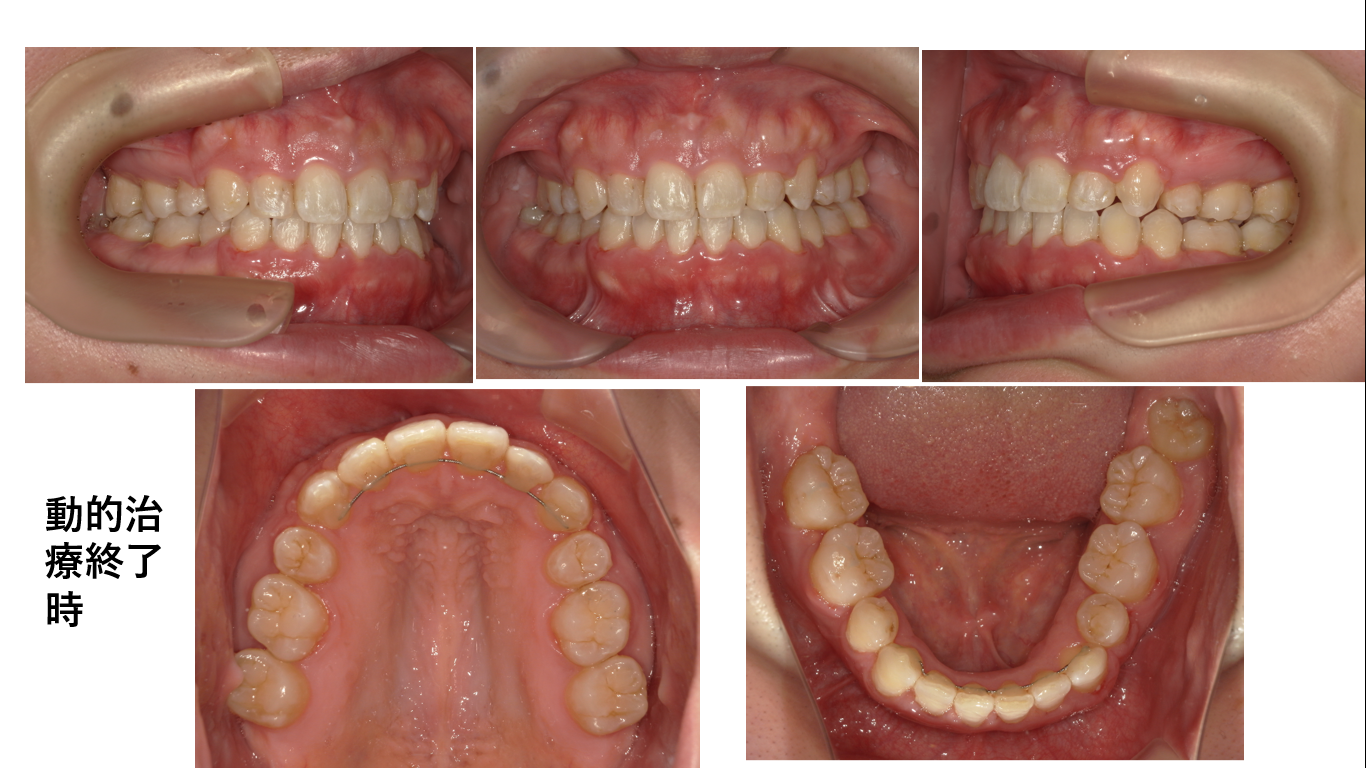

矯正症例143 AngleⅡ級2類、裏側矯正、舌側矯正

治療開始年齢24歳、治療期間3年、抜歯部位:下顎左右5番、上顎左右4番、治療費総額1,310,000(税込み)